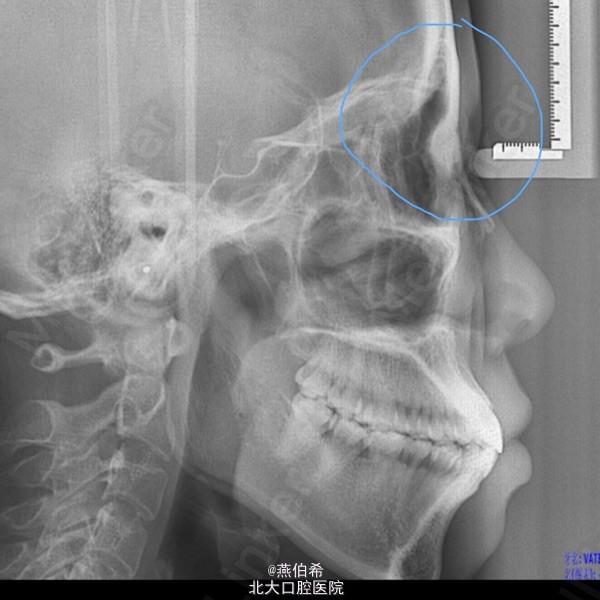

从侧位片看人种的面部差异

还记得头侧片上N(Nasion)点的定义吗?"鼻额缝的最前点"。你在量片子的时候能找到中国人的N点不?我怀疑绝大多数都是矇的。我们蒙古人种眼睛凸,眼眶浅,而高加索人种眼窝深,很好找N点。从当代的审美看,人家从遗传上就好看。